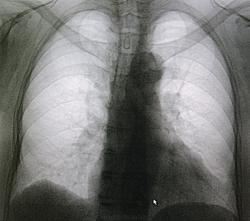

Пол пациента: Мужской пол Тип патологии: Инфекция Область исследования: Грудная клетка и верхние дыхательные пути Методы исследования: Rg Пациент средних лет, плановый осмотр, жалоб не предъявляет(незначительный кашель). https://radiomed.ru/sites/default/files/styles/case_slider_image/public/user/712/sl273319.jpg?itok=L3hNXDOC https://radiomed.ru/sites/default/files/styles/case_slider_image/public/user/712/sl273318.jpg?itok=wxMta4sk ID:9208 Сб, 20/11/2010 - 20:50 #1 Makcimalist Не на сайте Был на сайте: 11 лет 9 месяцев назад Зарегистрирован: 08.05.2010 - 14:28 Публикации: 1994 - снимки (репродукции по Петровичу) низкого качества, переделал бы снимки! -------------- "Просто, по видимости, не видеть логики в очевидных вещах - это тоже одно из свойств некоторых умов, наряду с грустными думами о свойствах ума других." © Vega 08/10/2011 Вс, 21/11/2010 - 01:38 #2 Петрович Не на сайте Был на сайте: 7 лет 3 месяцев назад Зарегистрирован: 22.03.2009 - 01:13 Публикации: 3908 Makcimalist wrote: - снимки (репродукции по Петровичу) низкого качества, переделал бы снимки!Верно! А то поговорить-то о пневмонии можно, но безответственно. Неоднозначно всё Вс, 21/11/2010 - 01:53 #3 Helios Не на сайте Был на сайте: 7 месяцев 4 недели назад Зарегистрирован: 06.08.2010 - 15:16 Публикации: 4417 Признаков не вижу.Не буду кидать больше камней в огород по поводу качества -и так досталось. Вс, 21/11/2010 - 02:01 #4 Петрович Не на сайте Был на сайте: 7 лет 3 месяцев назад Зарегистрирован: 22.03.2009 - 01:13 Публикации: 3908 Это кто ж посмел обидеть Ревнительницу Качества? Дайте ссылку! Неоднозначно всё Вс, 21/11/2010 - 10:14 #5 Helios Не на сайте Был на сайте: 7 месяцев 4 недели назад Зарегистрирован: 06.08.2010 - 15:16 Публикации: 4417 Петрович wrote: Это кто ж посмел обидеть Ревнительницу Качества? Дайте ссылку! Петрович, меня не так легко обидеть.Конечно, попытаться-то можно, но за последствия не ручаюсь. Это я пытаюсь подбодрить Игоря Артуровича-его случай. По поводу качества-понимаю, что хороший снимок и ду..(ой!) любой доктор прочитать сможет.Мне по душе больше качественные,Справедливый Вы наш! Вс, 21/11/2010 - 12:47 #6 Иван Тяпкин Не на сайте Был на сайте: 8 лет 4 месяцев назад Зарегистрирован: 27.09.2009 - 22:18 Публикации: 37 Пневмонии не вижу Вс, 21/11/2010 - 16:23 #7 Глазков Игорь А... Не на сайте Был на сайте: 9 месяцев 3 недели назад Зарегистрирован: 19.12.2008 - 20:41 Публикации: 1597 Helios wrote: Петрович wrote: Это кто ж посмел обидеть Ревнительницу Качества? Дайте ссылку! Петрович, меня не так легко обидеть.Конечно, попытаться-то можно, но за последствия не ручаюсь. Это я пытаюсь подбодрить Игоря Артуровича-его случай. По поводу качества-понимаю, что хороший снимок и ду..(ой!) любой доктор прочитать сможет.Мне по душе больше качественные,Справедливый Вы наш! ПОДДЕРЖКУ. Прийди к Себе Вс, 21/11/2010 - 18:41 #8 Катенёв Валенти... Не на сайте Был на сайте: 7 лет 4 недели назад Зарегистрирован: 22.03.2008 - 22:15 Публикации: 54876 А, Ваше мнение по поводу "пневмонии" какое Игорь Артурович? Вс, 21/11/2010 - 18:48 #9 Катенёв Валенти... Не на сайте Был на сайте: 7 лет 4 недели назад Зарегистрирован: 22.03.2008 - 22:15 Публикации: 54876 Меня сильно смущает на этих снимках только одно - "горбик" по контуру левого желудочка. Что УЗИ, что ЭКГ? Данных за аневризму левого желудочка нет? Приложения: Вс, 21/11/2010 - 18:52 #10 Катенёв Валенти... Не на сайте Был на сайте: 7 лет 4 недели назад Зарегистрирован: 22.03.2008 - 22:15 Публикации: 54876 Наличие пневмонии в данном случае совсен не воодушевляет.Приложения: Вс, 21/11/2010 - 18:56 #11 Дарья Не на сайте Был на сайте: 15 лет 4 недели назад Зарегистрирован: 22.09.2010 - 22:33 Публикации: 98 "горбик" по контуру левого желудочка-плевро-перикардиальная спайка? Вс, 21/11/2010 - 18:58 #12 Катенёв Валенти... Не на сайте Был на сайте: 7 лет 4 недели назад Зарегистрирован: 22.03.2008 - 22:15 Публикации: 54876 Дарья wrote: "горбик" по контуру левого желудочка-плевро-перикардиальная спайка? Может и спайка, а может и нет... Вс, 21/11/2010 - 21:08 #13 Глазков Игорь А... Не на сайте Был на сайте: 9 месяцев 3 недели назад Зарегистрирован: 19.12.2008 - 20:41 Публикации: 1597 пневмонии здесь нет. УЗИ сделать порекомендую. Прийди к Себе

Меня сильно смущает на этих снимках только одно - "горбик" по контуру левого желудочка. Что УЗИ, что ЭКГ? Данных за аневризму левого желудочка нет?

Наличие пневмонии в данном случае совсен не воодушевляет.

"горбик" по контуру левого желудочка-плевро-перикардиальная спайка?

Может и спайка, а может и нет...

пневмонии здесь нет. УЗИ сделать порекомендую.